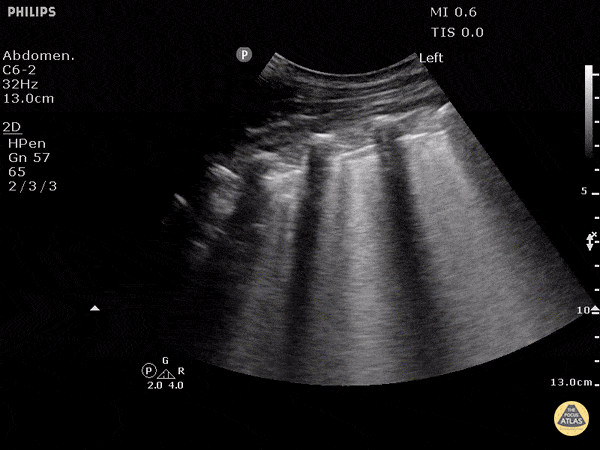

Prominent Finding(s) seen in this RUQ clip:

Ascites and Pleural Effusion with Jellyfish sign